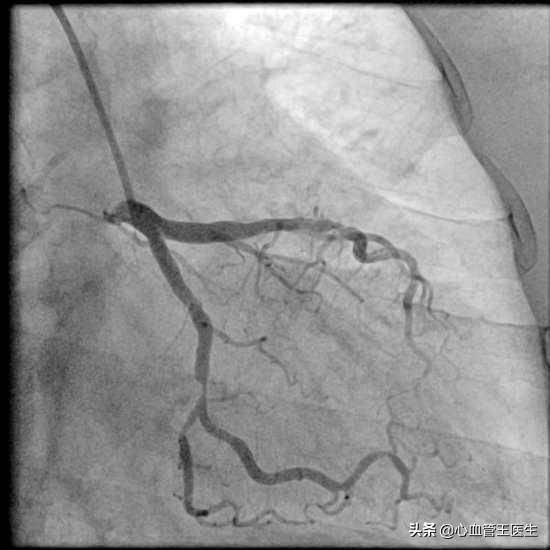

王医生:理论上做心脏CTA和心脏造影检查都能看出来哪根血管堵死了,但是现在高度怀疑得过心肌梗死,且已经出现心衰,所以还是建议直接做造影比较好。因为CT只是一种检查,如果发生血管狭窄,并不能治疗,甚至还得再次心脏造影。这样不但多花钱,而且还遭受两次辐射,受两次造影剂危害。造影一步到位,如相对CT更加准确,如果造影发现问题,还能当时就打通血管,或解决狭窄血管,免遭二次痛苦。

老周住院后,造影检查显示心脏左前方前降支血管中段完全堵塞,且已经有右侧血管的逆向血流,于是我们花费很长时间打通血管,在一定程度上能改善心肌缺血和心功能。